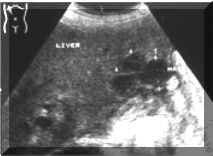

Metastatic

(Picture1).

Picture1.

Multiple,

small

metastases.